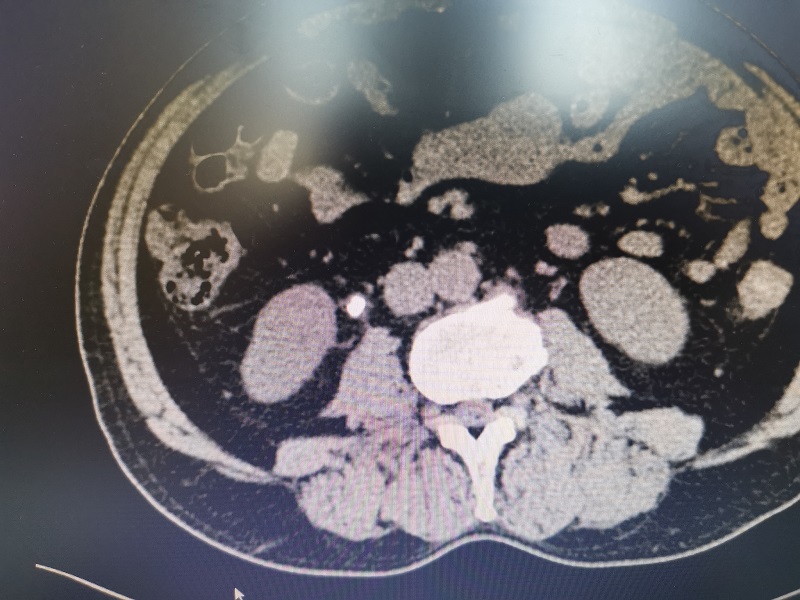

其中一例患者因“间断右侧腰部疼痛2月”入院,入院B超提示右侧输尿管上段可见一约15mm×6mm大小的强回声团块,行CT检查进一步确诊为输尿管结石。因该结石大于1厘米,若行激光碎石治疗,排石期长且感染风险高,经与家属沟通,同意行腹腔镜下输尿管切开取石术。